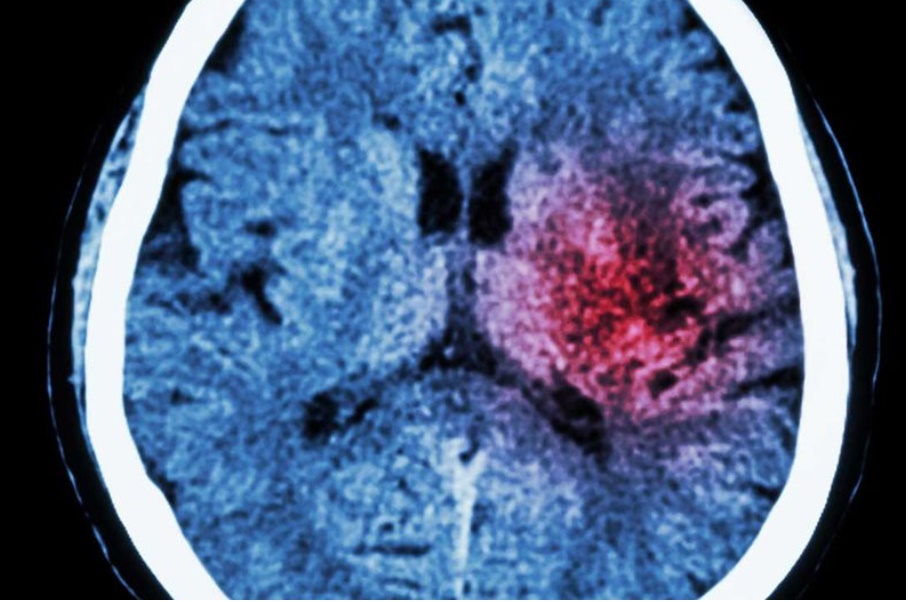

Dette er et kurs som omhandler Akutt svimmelhet i et hjerneslag perspektiv. Målet er å øke kompetanse for hva som kan forårsake akutt svimmelhet og hvordan vi kan differensiere disse klinisk. I tillegg vil kurset gå gjennom Helse Bergens lokale retningslinjer for bruk av e-stroke.